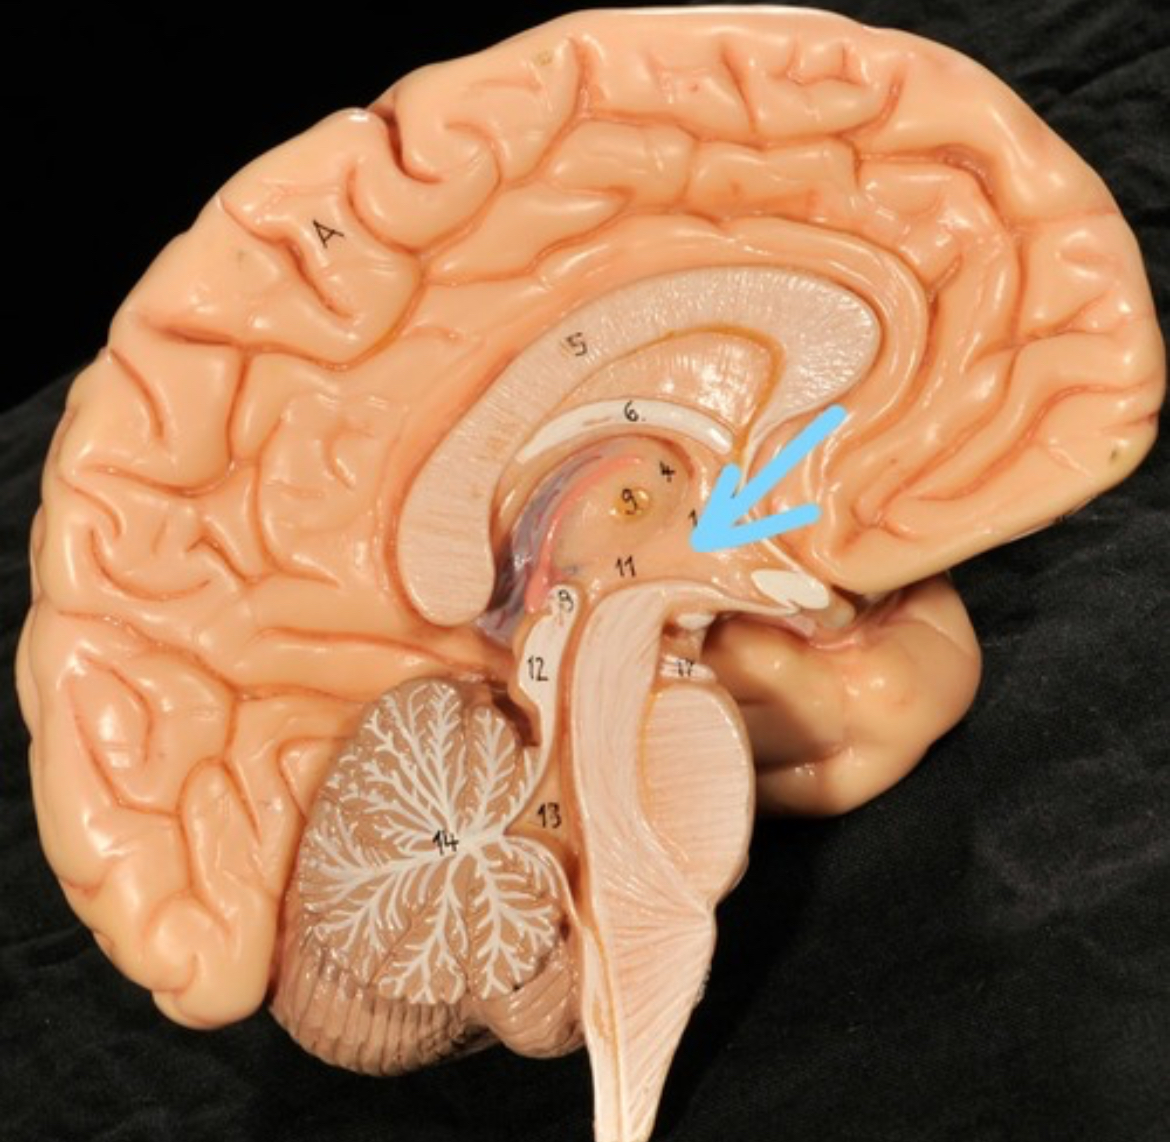

Corpus callosum

Diencephalon

Thalamus

3rd ventricle

Hypothalamus

Epithalamus (pink line)

Brain stem

Pons

Medulla oblongata

Choroid plexus of 3rd ventricle

Cerebral aqueduct (midrain)

4th ventricle

central canal